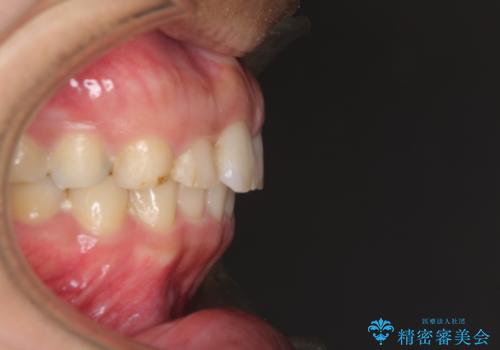

- 深い咬み合わせと前歯のデコボコ、奥歯の欠損を気にして来院された患者様です。

歯列矯正はインビザラインを使用し、矯正治療中の適切な時期に奥歯の欠損部位にインプラントを埋入することとしました。

矯正治療とインプラント治療を同じ歯科医師が担当することで、通常見られるような複数医院を行き来する煩雑さや、複数担当医の見解の違いによる治療の遅滞といった煩わしさは一切なく、スムーズに治療を進めることができました。

安定して咬めるようになり、患者様には大変満足していただきました。